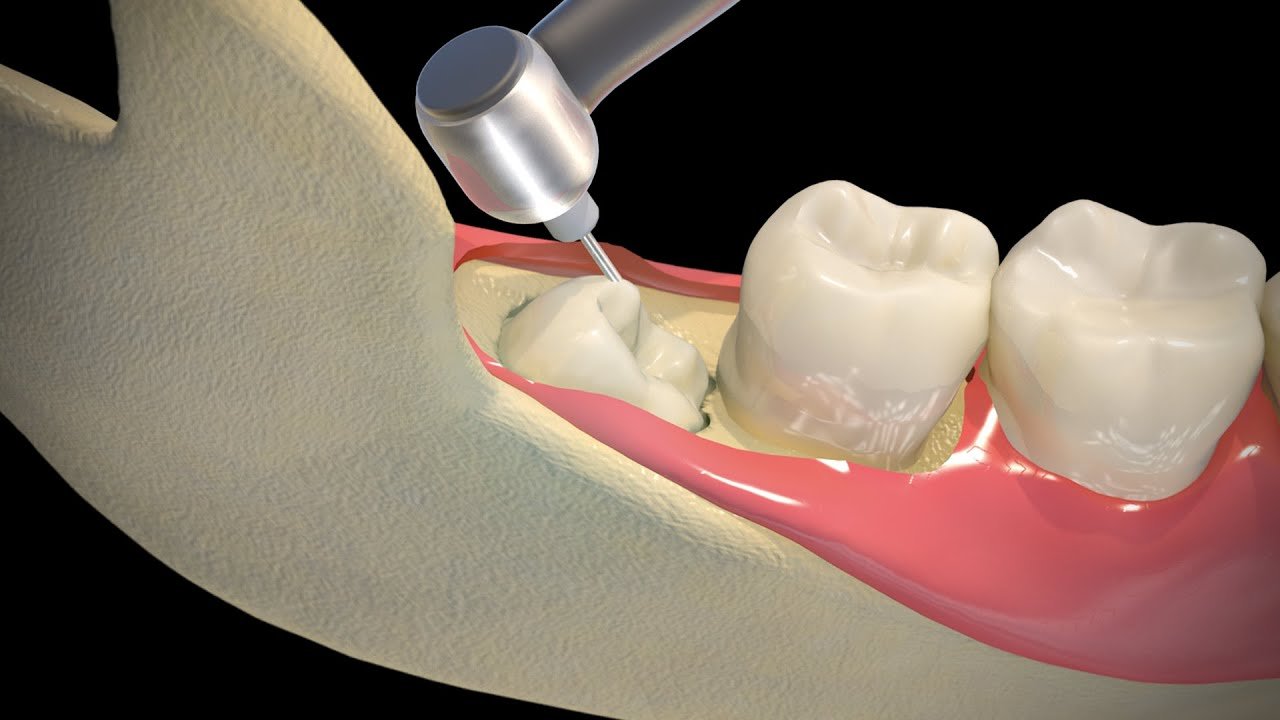

• Wisdom Tooth Extraction: This common procedure involves removing the third molars (wisdom teeth) which can cause pain, overcrowding, or infection if they don't erupt properly.